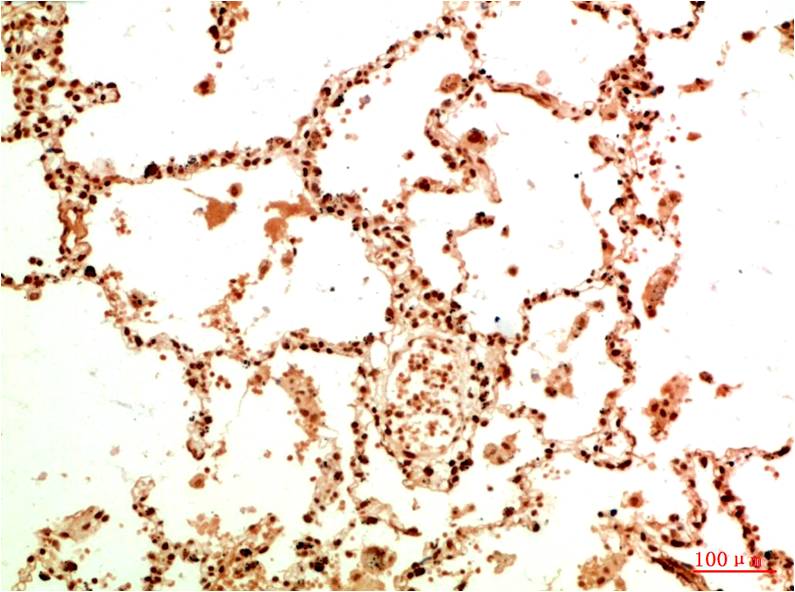

Product name: Acetyl NF kB P65(K314/K315) (5G11) Mouse mAb

Dilutions: IHC 1:100-200

Cellular localization: Cytoplasm,?Nucleus